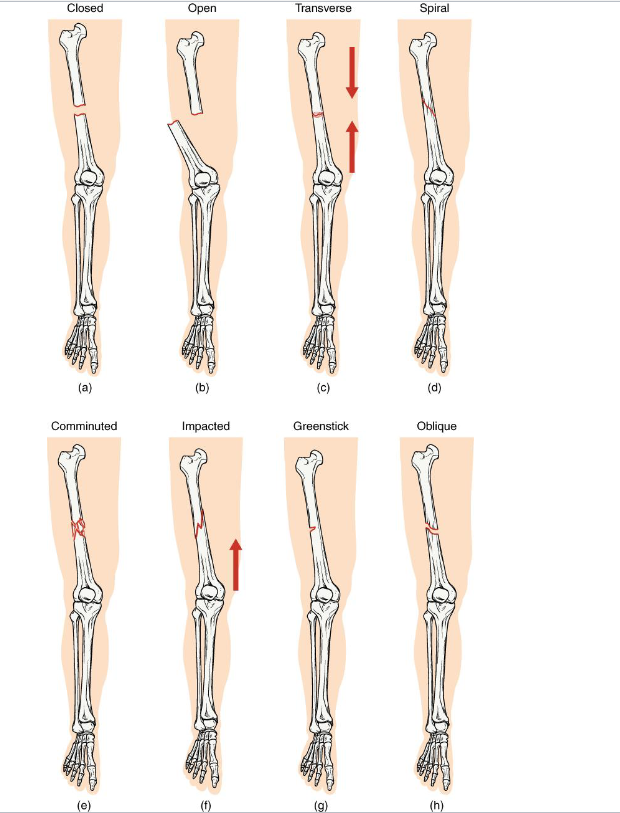

Fractures

<p>Joints and bones work together</p><p>When bones are stressed beyond capacity → Fractures</p><p></p>

Closed Fracture

<p><strong>Definition</strong>: Bone breaks but <strong>does not penetrate the skin</strong></p><p><strong>Mechanism: Usually caused by a direct blow or bending stress</strong></p><p><strong>Clinical note: Lower infection risk;</strong> easier to manage if aligned</p><p><strong>Key Concept</strong>: Skin remains intact → internal healing environment protected</p>

Open Fracture

<p><strong>Definition:</strong> Bone <strong>breaks through the skin </strong>(or skin is broken, exposing bone)</p><p><strong>Mechanism: High-energy trauma </strong>(ex: motor vehicle accident, gunshot)</p><p><strong>Clinical note: High infection risk and delayed healing.</strong></p><p><strong>Key concept</strong>: Requires surgical cleaning and fixation</p>

Transverse Fracture

<p><strong>Definition: Straight horizontal break</strong> across the bone shaft</p><p><strong>Mechanism</strong>: <strong>Perpendicular force t</strong>o long axis (ex: direct impact)</p><p><strong>Clinical note</strong>: Often stable if bone ends align well: heals predictably with immobilizaton.</p><p><strong>Key Concept: compression or bending directly across bone.</strong></p>

Spiral Fracture

<p><strong>Definition</strong>: Twisting or rotational fracture line around the bone</p><p><strong>Mechanism</strong>: <strong>Rotational force</strong> (ex: skiing, twisting fall, child abuse case)</p><p><strong>Clinical note</strong>: Jagged edges → difficult reduction; may damage surrounding soft tissue.</p><p><strong>Key Concept</strong>: Indicates torque forces; look for rotational injury pattern</p>

Comminuted Fracture

<p><strong>Definition: Bone is shattered into three or more fragments.</strong></p><p><strong>Mechanism: high impact trauma</strong> (ex: car accidents, falls from height)</p><p><strong>Clinical note:</strong> Complex repair; may require surgical plates/pins; slow healing.</p><p><strong>Key concept: represents severe energy transfer </strong>→ bone fragmentation</p>

Impacted fracture

<p><strong>Definition: One fragment is driven into another within the same bone</strong></p><p><strong>Mechanism</strong>: Axial loading (ex: landing hard on extended arm/leg)</p><p><strong>Clinical note: Bone ends jammed together;</strong> limb may apper shortened</p><p><strong>Key concept:</strong> common in falls - the bone compresses itself</p>

Greenstick Fracture

<p><strong>Definition: Incomplete break </strong>- bone bends and cracks on one side</p><p><strong>Mechanism</strong>: common in children (softer, more flexible bone)</p><p><strong>Clinical note: Often associated with forearm fractures in pediatrics.</strong></p><p><strong>Key concept</strong>: compare to bending a green twig - it splinters but doesnt snap</p>

Oblique Fracture

<p><strong>Definition: Diagonal fracture line</strong> across the bone shaft.</p><p><strong>Mechanism</strong>:<strong> angles force applied along the long axis.</strong></p><p><strong>Clinical note:</strong> Sharp ends may lead to displacement; requires stabilization.</p><p><strong>Key concept: often confused with spiral fractures -</strong> but lacks twist pattern</p>

One fracture but Many types

knowt flashcard image